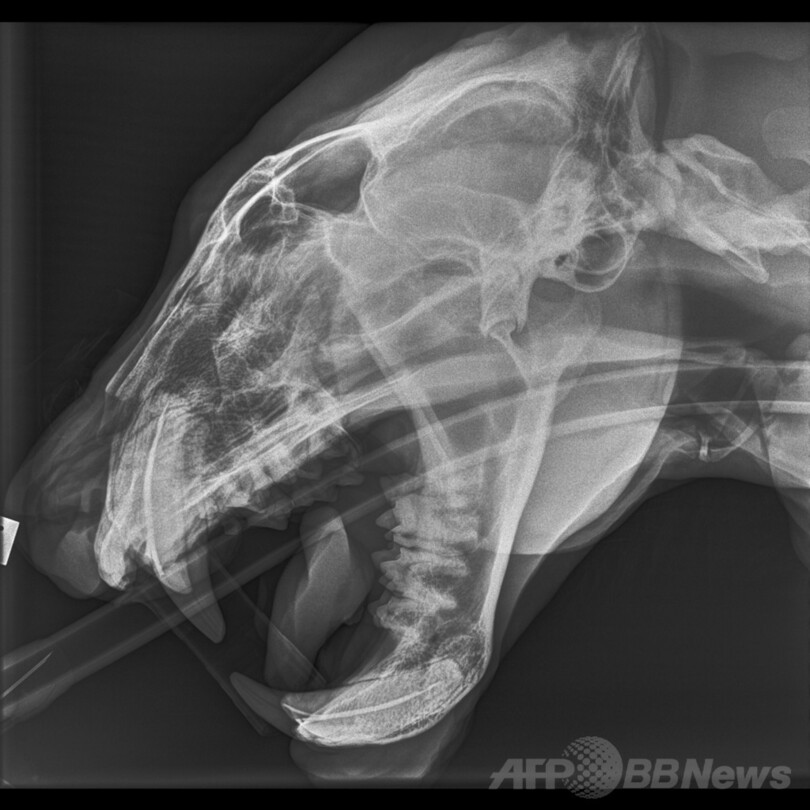

【2月22日 AFP】ニュージーランドの首都ウェリントン(Wellington)にあるウェリントン動物園(Wellington Zoo)で21日、同園で飼育されているオスのトラ「ローカン(Rokan)」のメディカルチェックが行われた。体重120キロ、年齢17歳になるローカンは、最近いつもと違う元気のない様子だったため、獣医師たちの判断により、全身麻酔をかけた上で検査が施された。(c)AFP